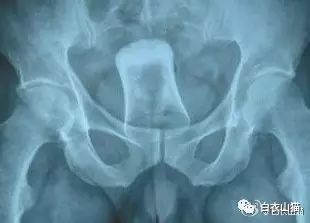

这是做饺子皮用的擀面杖。对,全部塞进去了。你知道怎么看男女吗?看骨盆的角度。

也是一个白炽灯灯泡,是小头先塞进去。看出来男女了吗?